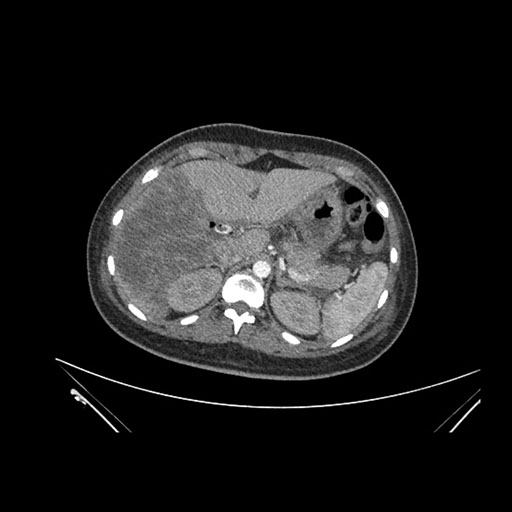

Axial Arterial

Imaging analysis

Based on initial findings, which issue(s) would you be most concerned about?